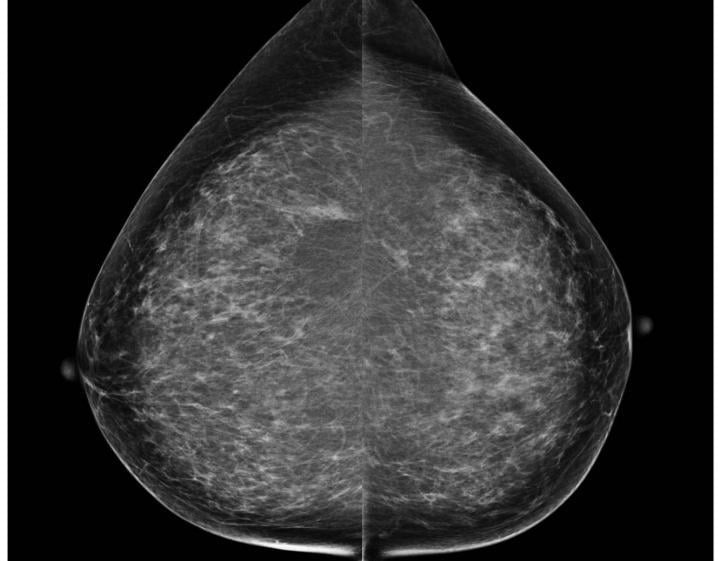

December 9, 2014 — A study of breast cancers detected with screening mammography found that strong family history and dense breast tissue were commonly absent in women between the ages of 40 and 49 diagnosed with breast cancer. Results of the study were presented at the annual meeting of the Radiological Society of North America (RSNA).

The retrospective study, conducted at UCSF, included 136 women between the ages of 40 and 49 with breast cancer identified by screening mammography between 1997 and 2012. Symptomatic patients undergoing diagnostic mammography and those with a personal history of breast cancer were excluded from the study. Patient family history, breast density, type of malignancy, lymph node status and tumor receptor status were recorded.

Of the 136 breast cancer cases identified, 50 percent were diagnosed as invasive, and 50 percent were diagnosed as ductal carcinoma in situ (DCIS), an early noninvasive form of breast cancer, although 88 percent of DCIS cases were intermediate or high grade.

A very strong family history was absent in 90 percent of patients, and extremely dense breast tissue was absent in 86 percent. Seventy-eight percent of patients had neither strong family history nor extremely dense breasts, including 79 percent of the cases of invasive disease.

"Our results show that by exclusively using a risk-based approach to screening mammography, we could potentially miss more than 75 percent of breast cancers in women in their 40s, thereby eliminating most of the survival benefit from screening mammography that has been previously shown in randomized controlled trials," Joe said.

Routine annual screening mammography has traditionally been recommended by organizations such as the American Cancer Society (ACS) and the American Medical Association (AMA) for all women beginning at age 40. In 2009, the United States Preventive Services Task Force (USPSTF) issued controversial new guidelines recommending screening with mammography every two years beginning at age 50.

"Based on our current knowledge and evidence shown in previous trials, it is still safest to get annual mammograms starting at age 40 in order to maximize the survival benefit of screening mammography," Joe said.